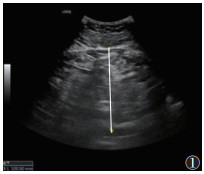

1.2 仪器与方法615例均行超声检查,采用GE20彩色多普勒超声诊断仪。受试者取仰卧位,伸展右上肢至头部,充分扩展肋间隙。选用凸阵探头(频率2~5 MHz),垂直放置探头,通过肋间隙对肝Ⅴ段行常规超声检查,并根据肝脏回声强度、肝肾回声对比、肝内血管和膈肌的清晰度,判断脂肪肝程度(无、轻度、中度和重度)[4];测量内脏脂肪厚度(visceral fat thickness,VFT),将探头置于脐上1 cm,测量双侧腹直肌间腹白线至腹主动脉前壁的距离[5](图 1),结果取双侧平均值。使用线阵探头(频率2~9 MHz)测量皮下脂肪厚度(subcutaneous fat thickness,SFT):将探头置于脐上1 cm,左右移动探头测量腹部两侧皮肤至腹直肌外缘距离(图 2),最终结果取双侧平均值[5]。激活UGAP模式,嘱患者屏住呼吸3~5 s,记录不同帧上连续回波UGAP-AC平均值,注意避开胆管、血管等伪影(图 3)。

| 图 1 常规超声测量腹部内脏脂肪厚度(VFT)示意图 |